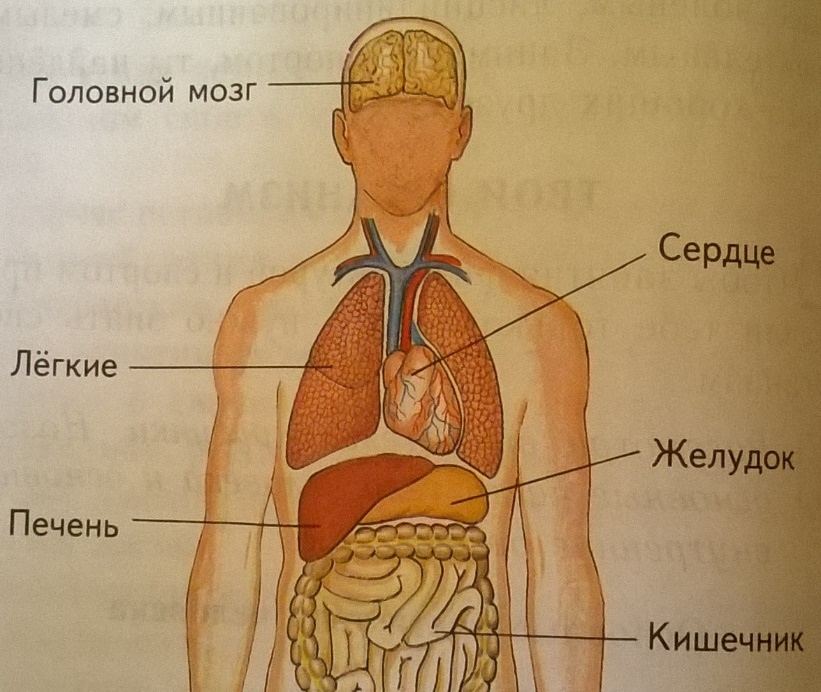

Анатомия желудка и сердца: визуализация и изучение

Раздел: Фотопанорама